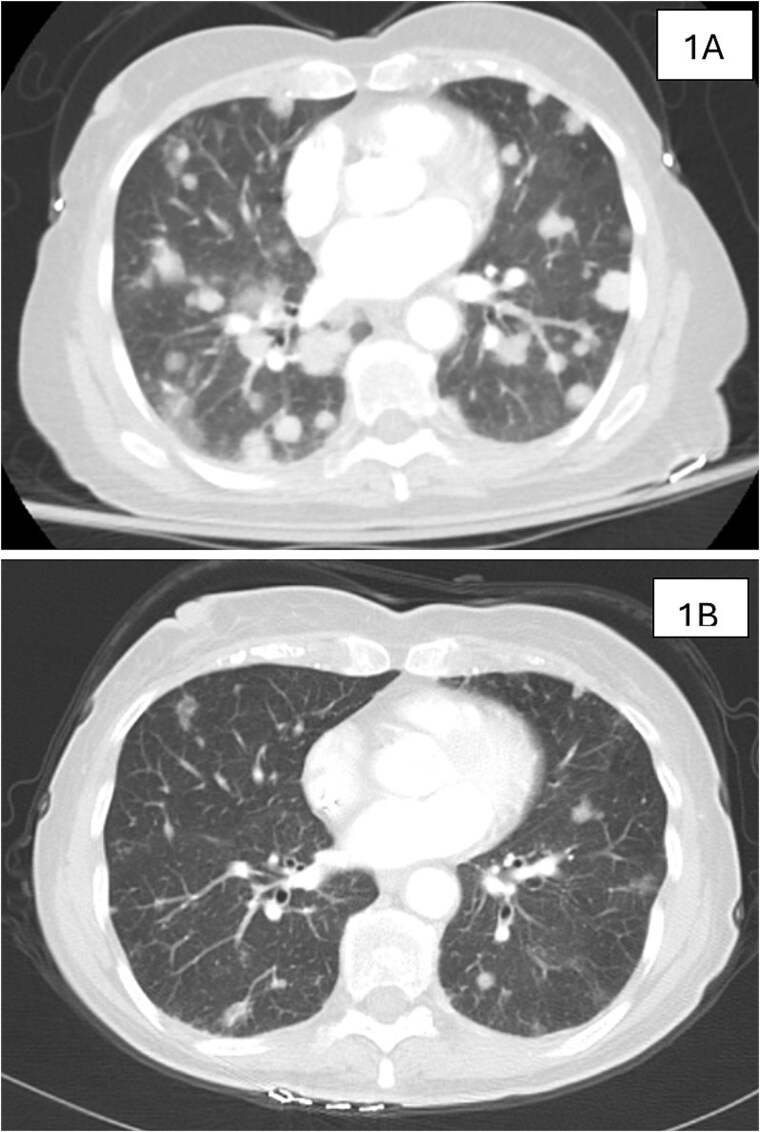

Late recurrence of ovarian cancer is exceedingly rare. We report a case of adenocarcinoma of Müllerian origin that developed 22 years after hysterectomy and bilateral salpingo-oophorectomy (BSO) for ovarian cancer in an 81-year-old woman with a pathogenic BRCA1 mutation. The patient underwent six cycles of reduced-dose carboplatin and paclitaxel, achieving remission with a dramatic decline in CA-125 levels. Women with BRCA mutations have a significantly increased risk of ovarian/tube/peritoneal cancer. Although risk-reducing BSO effectively decreases the risk of ovarian and fallopian tube cancers, the risk of peritoneal cancer remains substantial. This case not only illustrates the persistent lifetime risk of ovarian/tube/peritoneal cancer despite BSO but also underscores the need for reevaluation of prophylactic surgical strategies, particularly regarding the extent of peritoneal resection, in BRCA mutation carriers. Additionally, this case report demonstrated the efficacy of dose-modified chemotherapy for BRCA-associated cancers. Further research is warranted to refine surgical and therapeutic strategies for patients with BRCA mutation.